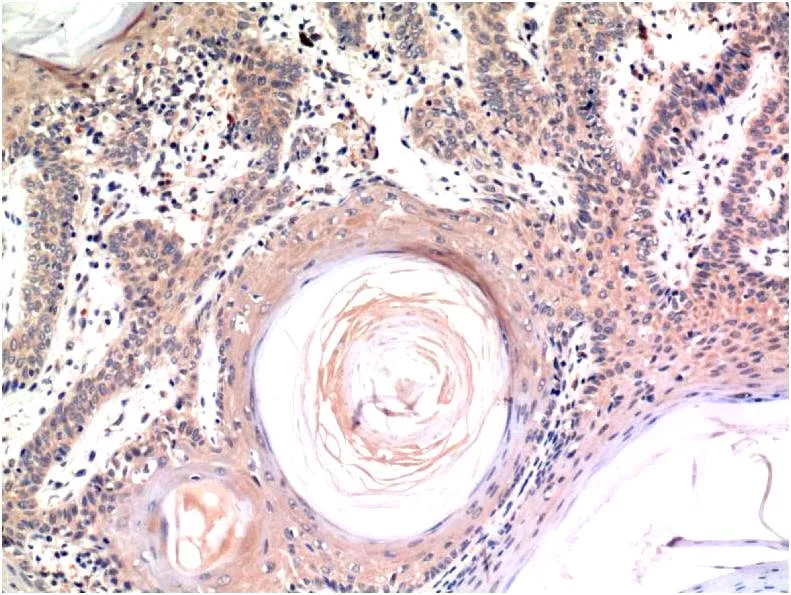

Ki67 (10B6) Mouse Monoclonal Antibody

Cat: AMM00719